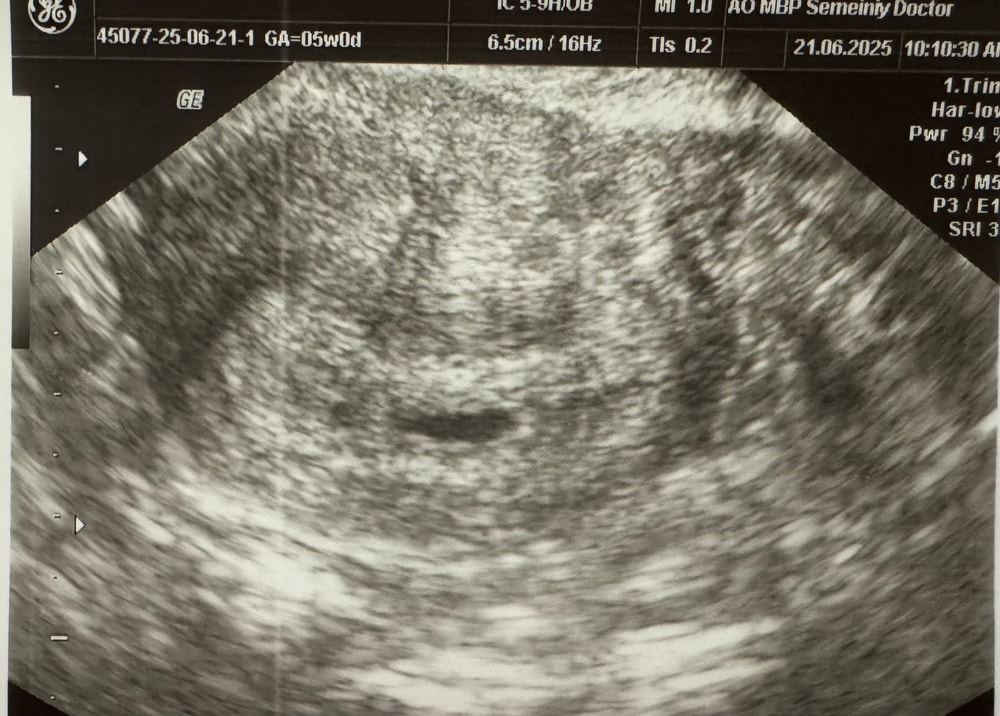

5 недель узи и хгч

Девочки, переживаю, хгч растет хорошо, а по УЗИ ПЯ малюсенькое.

Срок 4 недели 6 дней.

Ходила сегодня на УЗИ, плодное яйцо в матке, но крошечное 3.8мм, не знаю что и думать. Почему хгч так бодро растет, а ПЯ такое маленькое?